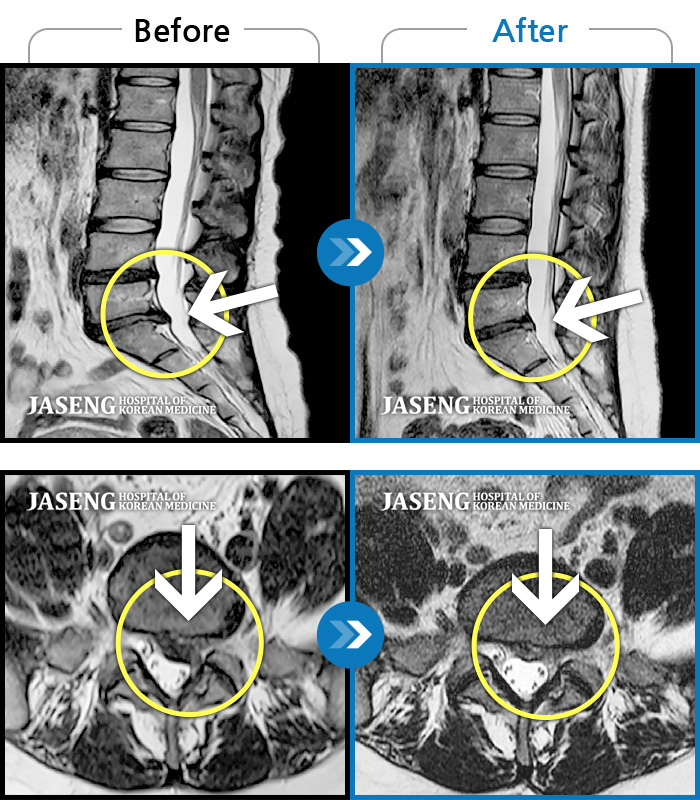

• 허리디스크